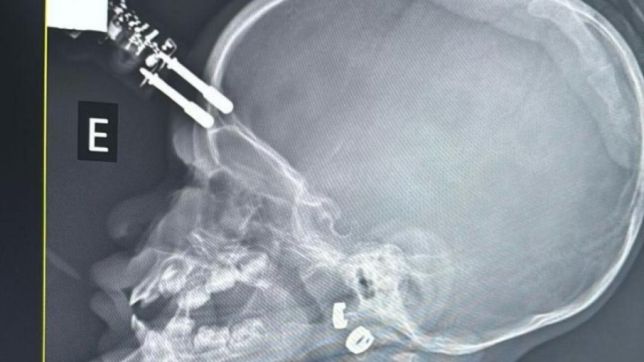

Bebê fica com carregador cravado na testa após cair de cama